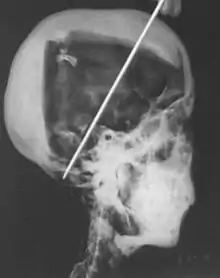

- 1968; A portable X-ray machine was used to examine the mummy of Tutankhamun in his tomb in the Valley of the Kings by researcher R. G. Harrison. These images indicated an age of death of around 18–20 years based on bone age from a study of the limb lengths, as well as tooth analysis. The rumoured cause of death of tuberculosis was also ruled out during this study. A new hypothesis was formed that Tutankhamun died because of blunt force trauma to the head, due to a depressed fracture found on the skull.[6]

A recent CT scan of Tutankhamun in 2006 was able to provide evidence against the 'homicide theory'.[2][6] A depression fracture noted on the skull from X-rays taken 30 years previously was found to be a post-mortem injury rather than a cause of death.[6] The hole in the head had been created in order to continue the embalming process of mummification.[10] This CT investigation was also able to confirm Tutankhamun's age of death as nineteen and disprove the idea that the young pharaoh had suffered from scoliosis; rather the bend in his spine was from additional post-mortem damage to the body.[10]